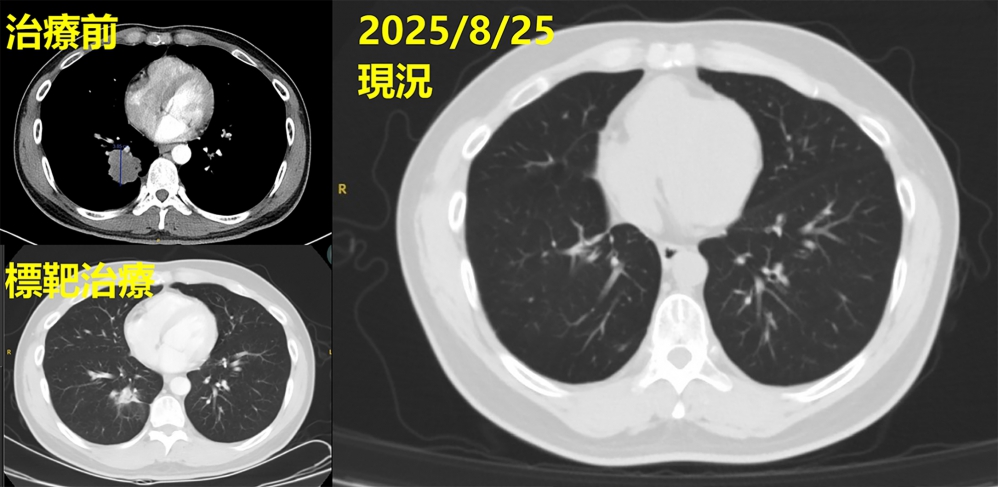

彰基醫學中心曾於3年前成功治癒一名合併腦轉移的肺腺癌個案,透過跨科團隊精準治療,病人終於康復重返職場,彰基說,患者是41歲許姓男子,從事文具業務,為家裡經濟支柱,三年前(2022年)6月某日清晨,右側肢體突然無力、抽搐,繼而倒地不起,許男由家人送彰基急診,經電腦斷層和核磁共振檢查,發現腦部有約3.1公分腫瘤,進一步追蹤,右下肺有4公分腫塊,醫師確診肺腺癌合併腦轉移。

林主任說,病人入院時,醫院依臨床流程完成初步基因檢測,不能使用突變標靶,團隊持續評估治療方向,協助病人參與國衛院臨床基因試驗,最終發現具EGFR exon 19 deletion突變,可以申請第三代EGFR標靶藥物,讓治療更具針對性和精準性。

林聖皓醫師說,經一段時間影像追蹤,顯示肺部腫瘤從原本的4公分縮小為2.8公分,控制成效顯著,儘管標靶藥物初期控制良好,許姓患者仍出現神經症狀,胸腔內科隨即啟動跨科整合照護,與神經外科孫立偉醫師合作完成腦部腫瘤手術,術後雖神經功能逐漸恢復,但考量治療效果,經與胸腔外科召開跨科討論後,由洪維亨醫師進行「肺葉切除」手術,達成更徹底控制。